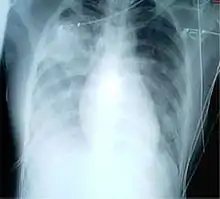

For a case to be considered probable, a chest X-ray must be indicative for atypical pneumonia or acute respiratory distress syndrome.

The WHO has added the category of "laboratory confirmed SARS" which means patients who would otherwise be considered "probable" and have tested positive for SARS based on one of the approved tests (ELISA, immunofluorescence or PCR) but their chest X-ray findings do not show SARS-CoV infection(e.g. ground glass opacities, patchy consolidations unilateral).[10][11]

The appearance of SARS-CoV in chest X-rays is not always uniform but generally appears as an abnormality with patchy infiltrates.[12]